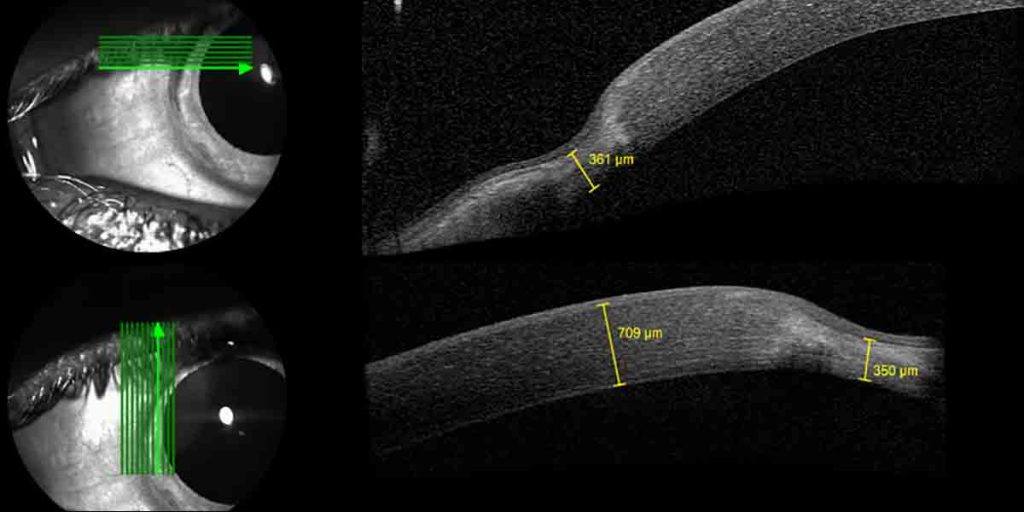

Esta imagem de OCT mostra um afinamento da córnea na periferia (os bordos) da córnea)

Sabemos mais sobre a patologia: a doença é caracterizada pelo adelgaçamento da margem (bordos) da córnea onde esta se encontra com a parte branca do olho (a esclerótica). O afinamento começa normalmente na parte superior da margem, progride e envolve toda a circunferência da periferia da córnea. A doença resulta normalmente no crescimento de novos vasos sanguíneos - neovascularização - e na formação de cicatrizes e depósitos de lípidos (normalmente vistos como opacidades estromais pontuais finas e amareladas) na margem. À medida que a degenerescência progride, conduz normalmente a um aumento do astigmatismo contra a regra ou oblíquo. A córnea pode ficar gravemente enfraquecida, podendo ocorrer rupturas espontâneas da membrana de Descemet que resultam em líquido interlamelar ou quistos da córnea. Embora a perfuração espontânea seja rara, mesmo um pequeno traumatismo pode perfurar a córnea. A questão é: como é que a DTM pode ser tratada?